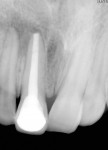

A 15-year-old male patient presented with a primary complaint of a discolored maxillary anterior tooth. Clinical examination revealed fracture in both the upper right and upper left central incisors (Figure 1). The patient had a history of trauma that occurred 8 years previously. No significant medical history was reported. A periapical radiograph demonstrated an incompletely formed root apex and a large radiolucent area around the upper right central and lateral incisors (Figure 2). The upper right central incisor elicited negative responses on electric as well as thermal pulp testing, although adjacent and contralateral incisors elicited positive responses. Based on subjective and objective findings, a diagnosis was made of Ellis Class IV fracture in the upper right central incisor and Ellis Class I fracture in the upper left central incisor. A decision was made to perform apexification in the upper right central incisor along with a composite restoration in the upper left lateral incisor.

With a rubber dam in place and after access to the pulp chamber was gained, a working length radiograph of the upper right central incisor was taken (Figure 3). The working length was established 1-mm short of the radiographic apex. Cleaning and shaping was carefully performed using stainless-steel K-files. Copious irrigation with alternating solutions of 2.5% sodium hypochlorite and 17% EDTA was conducted throughout the cleaning and shaping procedure. After drying the canal system with paper points, calcium hydroxide paste (Metapex™, MetaBiomed, www.meta-biomed.com) was placed in the root canal system for 2 weeks, and a temporary coronal seal was established with Cavit™ (3M ESPE, www.3MESPE.com) (Figure 4). Calcium hydroxide was used to disinfect the root canal system in order to reduce root canal infection below a certain threshold level. After 2 weeks of Ca(OH)2 therapy, dressing was removed from the root canal system using sodium hypochlorite irrigation and endodontic files. Small pieces of CollaTape® (Zimmer Dental, www.zimmerdental.com), a synthetic collagen material, were gently compacted using hand pluggers to produce a barrier at the level of the apex. Gray MTA-Angelus (Angelus, www.angelus.ind.br) plug was placed in the canal with a carrier and pluggers to form an apical plug approximately 4-mm thick. Placement of MTA was confirmed radiographically (Figure 5). A small amount of Ca(OH)2 was extruded into the periapical region during removal (Figure 5). A sterile moist cotton pellet was placed over the MTA, and the access cavity was sealed with Cavit. The patient was recalled after 24 hours, and hardness of the apical barrier was checked at the follow-up appointment. Subsequently, backfill was performed using Obtura (Obtura Spartan Endodontics, www.obtura.com) (Figure 6). The access cavity was sealed and both fractured teeth restored with composite resin (Figure 7). The patient was recalled after every 3 months to check the vitality status of the upper right lateral incisor. The tooth was restored with a porcelain-fused-to-metal (PFM) crown, and periapical healing was confirmed by a radiograph at 1 year (Figure 8). The upper right lateral incisor elicited positive response on electric as well as thermal pulp testing after 1 year.